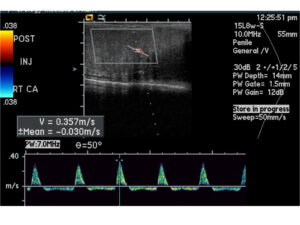

A disfunção erétil (DE) afeta muitos homens e pode ter diversas causas, desde fatores psicológicos até problemas vasculares. Para um diagnóstico preciso, um dos exames